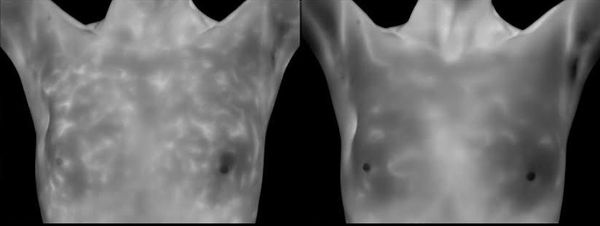

For women working to better their health, Insight Thermal Imaging in Spokane offers thermography as a powerful tool that allows you to see changes over time. See for yourself how life changes can help reverse the breast disease process. Our MammaCare certified clinical breast exams in Spokane can provide valuable information in the early detection of breast disease.